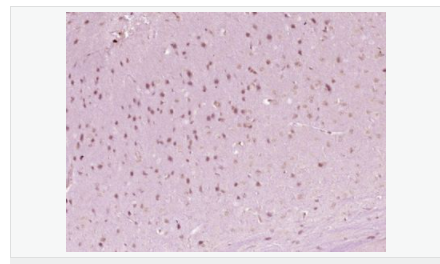

| 產(chǎn)品應(yīng)用 | WB=1:500-2000 ELISA=1:5000-10000 IHC-P=1:100-500 IHC-F=1:100-500 ICC=1:100-500 IF=1:100-500 (石蠟切片需做抗原修復(fù)) not yet tested in other applications. optimal dilutions/concentrations should be determined by the end user. |